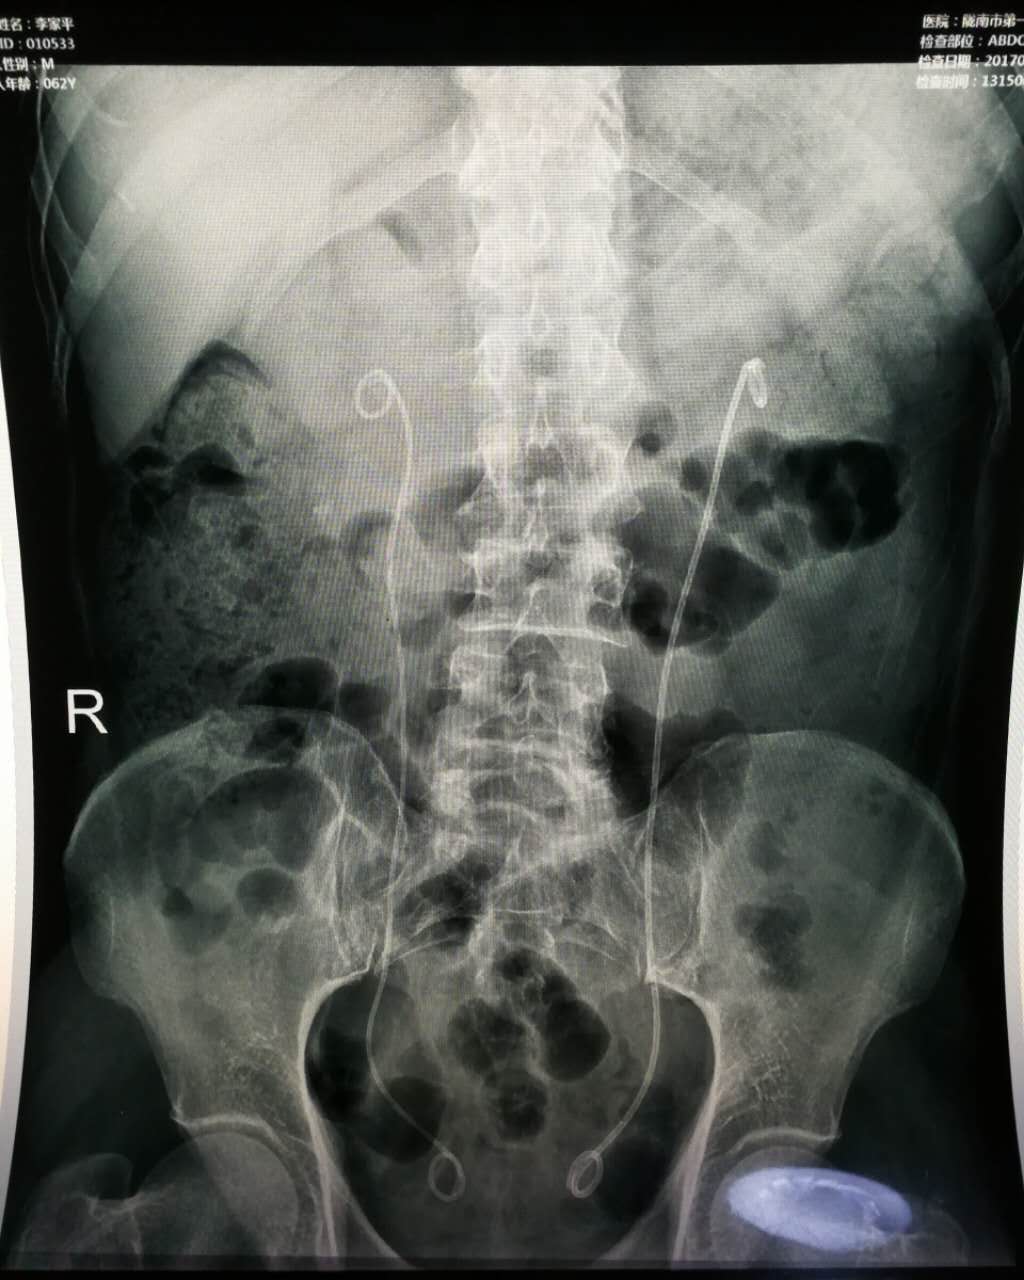

近日,我院泌尿外科成功开展复杂性上尿路结石输尿管硬镜联合输尿管软镜碎石术,术程顺利,目前患者已康复出院。

患者,老年男性,双侧输尿管结石,右肾结石,双肾积水,曾因泌尿系结石先后就诊于省级医院行手术治疗,此次因双肾积水,肾功能不全经多方打听来我院泌尿外科就诊。科室主任李朝明及其团队认真研究患者病情,综合考虑患者年龄、病史、手术史等,积极完善术前检查后,最终决定选择输尿管硬镜联合输尿管软镜为患者同时行双侧输尿管结石及右肾结石手术治疗。手术过程顺利,术后患者恢复良好,疗效显著。

我院泌尿外科一直关注本专业最前沿、最有效、最安全最高的微创技术,该手术的顺利开展,标志着我院泌尿外科在输尿管硬镜联合软镜治疗方面实现了新的突破,在治疗复杂性上尿路疾病方面又跨上了新的台阶,必将对上尿路结石的诊治产生深远的影响。